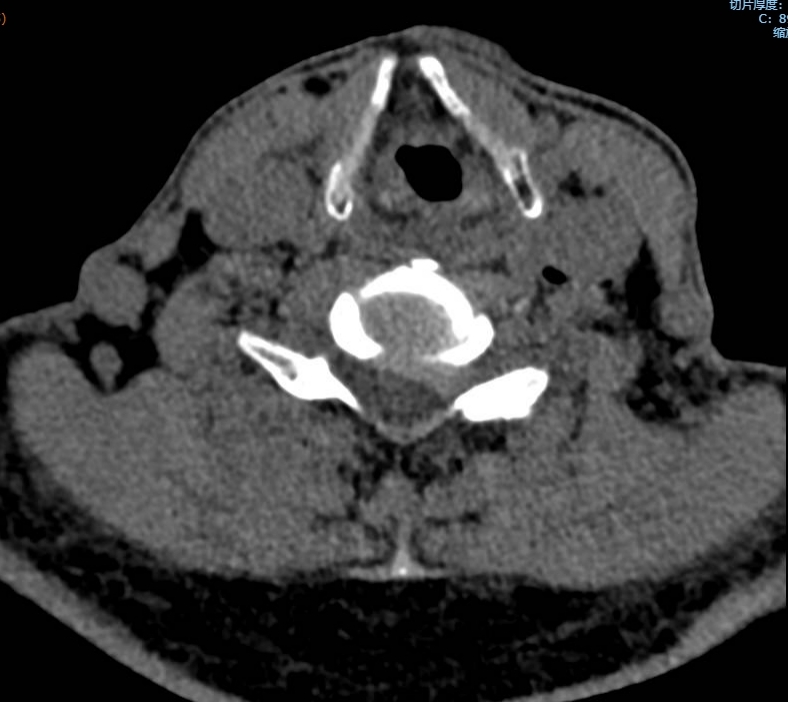

黃大伯今年70歲,入院前10多天出現(xiàn)左側(cè)肩背部疼痛及左上肢疼痛、麻木,患病以來根本不能平臥,就連睡覺也只能一直坐著,在院外治療后病情無緩解,反而加重,怎么回事呢?輾轉(zhuǎn)來到瀘州市中醫(yī)醫(yī)院疼痛科治療。由于疼痛嚴(yán)重,外加嚴(yán)重缺乏睡眠,黃大伯入院時(shí)焦慮、精神狀態(tài)很差。看著他急切想解除痛苦的眼神,疼痛科醫(yī)生團(tuán)...